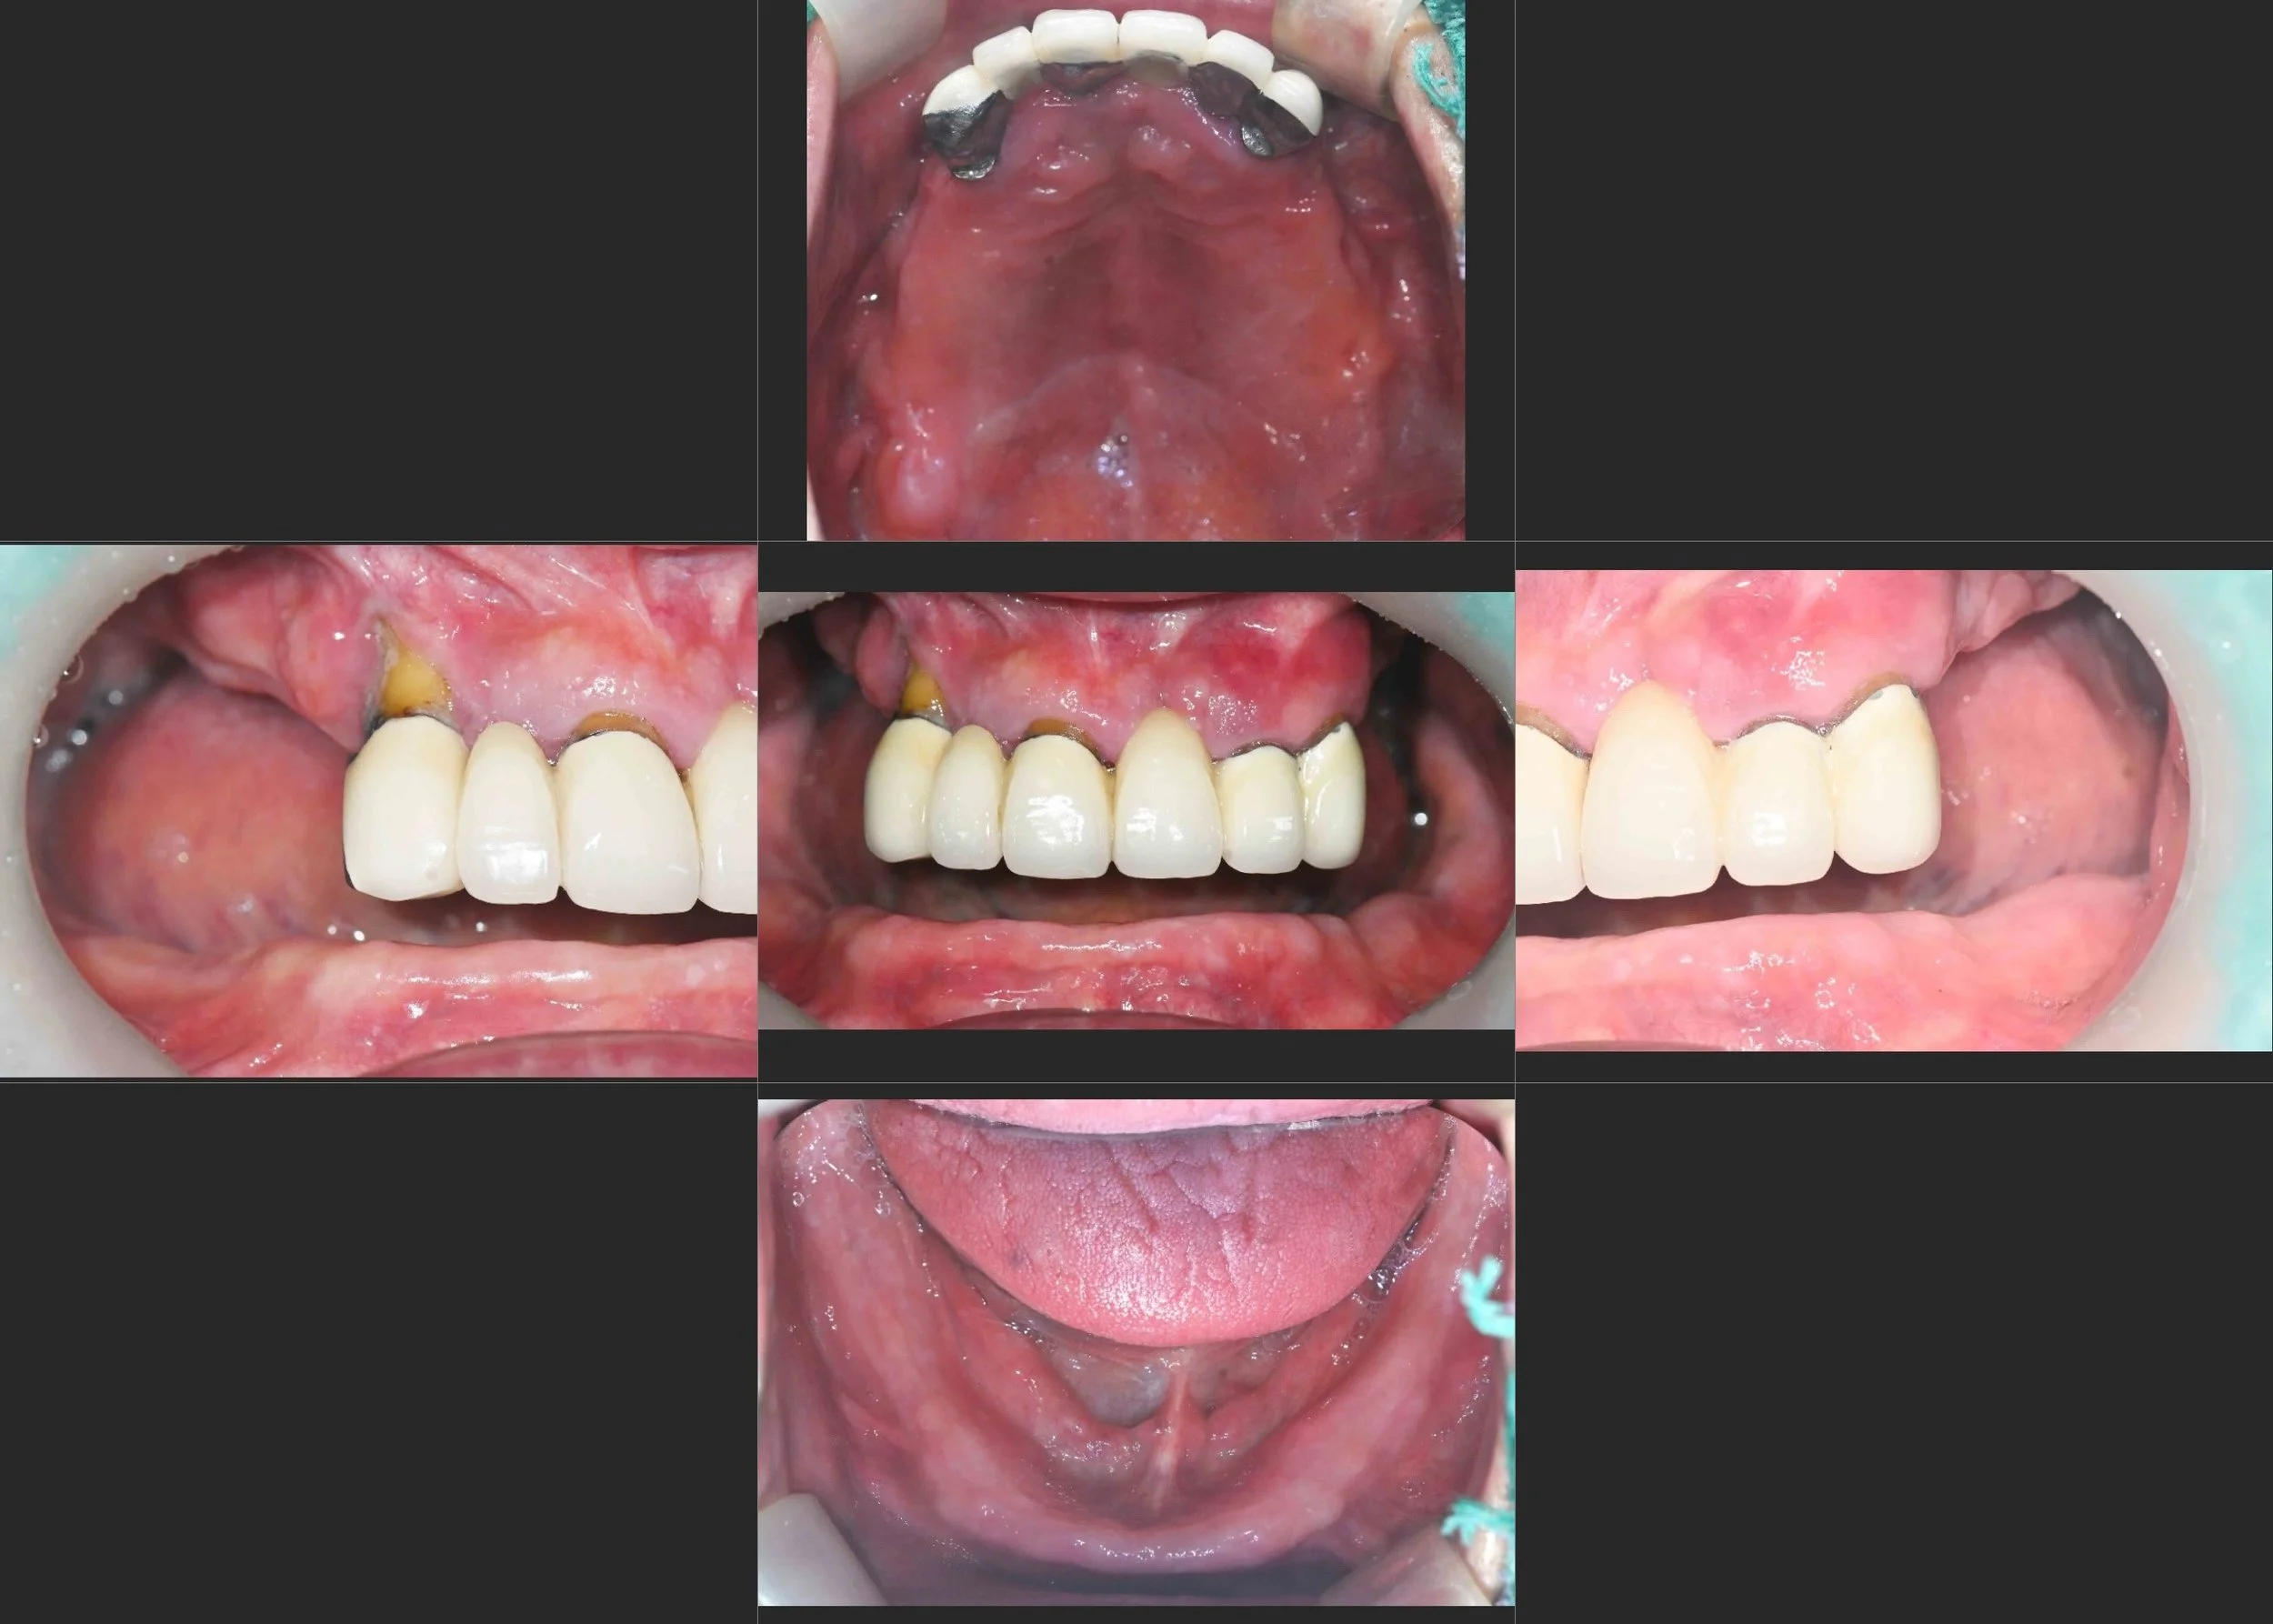

INTRA ORAL - BEFORE

• Long-term Denture Wear: Years of relying on removable partial dentures had led to progressive disuse atrophy of the periodontal tissues and underlying alveolar bone.

• Failing Anterior Bridge: A pre-existing maxillary anterior bridge had failed, causing localized but severe vertical and horizontal bone loss in the aesthetic zone.

• Complete Occlusal Failure: With no stable posterior stops and a failing anterior segment, the patient's masticatory efficiency was nearly non-existent.